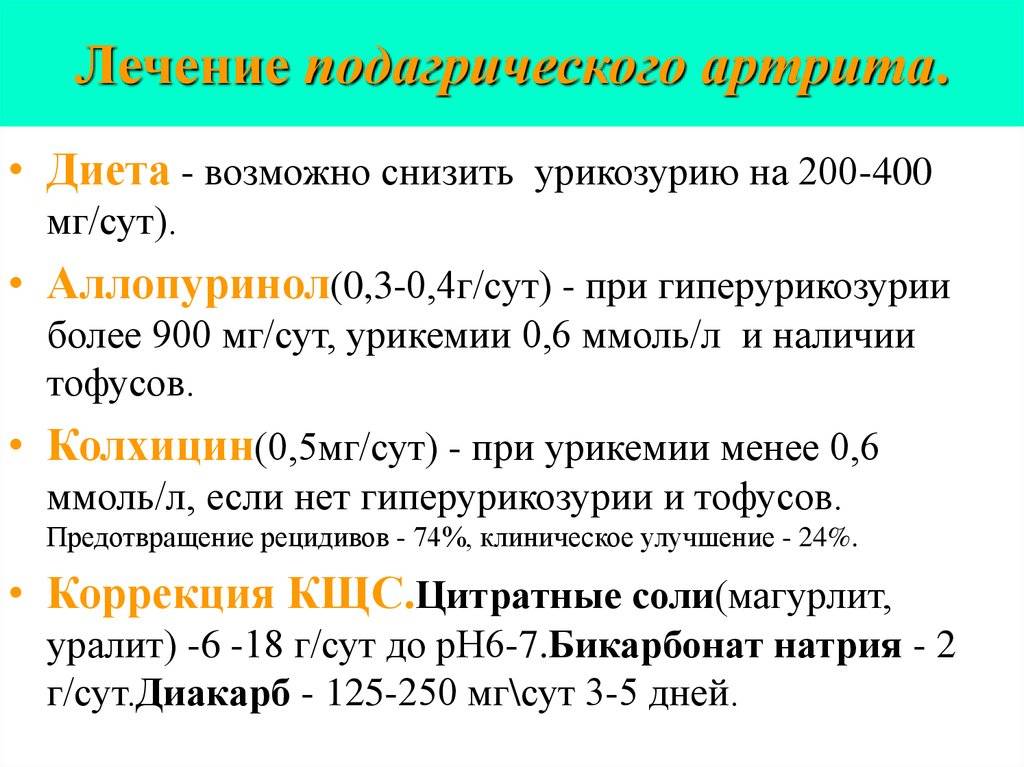

4. Подагрический артрит – это болезнь нарушения обмена веществ. В суставах откладывается соль мочевой кислоты. Отличительный признак – поражение сустава большого пальца стопы. Чаще всего заболевают любители вкусно и обильно поесть и выпивающие ежедневно много вина. Лечится такой артрит диетой и антибиотиками.

Подагра вызывает приступы острой боли в суставах. Причина ее — высокий уровень мочевой кислоты (продукт выделения) в крови, которая кристаллизуется и откладывается в суставах. Повышенное содержание мочевой кислоты объясняется и недостаточной функцией почек. Часто поражается только один сустав, обычно большой палец на ноге. Во время приступа происходит покраснение и повышение температуры кожи на пораженном суставе, он опухает, возникает сильная боль.

Приступы подагры можно предотвратить, уменьшив потребление алкоголя и исключив из рациона печень и другие субпродукты, птицу, горох и бобы, так как в них содержится большое количество пурина — вещества, способного повышать уровень мочевой кислоты в крови.